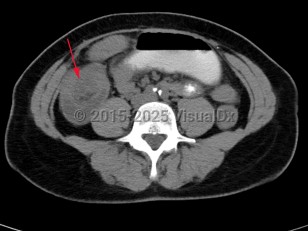

Intussusception is a telescoping or invagination of a part of the intestine into the lumen of an adjacent segment. Intussusception can present with variable severity. It can present with bowel ischemia and perforation with need for emergent surgical intervention, or it can present as relaxing / remitting abdominal pain of unclear etiology with intermittent symptoms and no signs of systemic illness. Jejunojejunal, jejunoileal, ileoileal, ileocolonic, and colocolonic are all types of intussusception that can occur, with the majority involving the small intestine.

Intussusception occurs in children and adults. It is the most common cause of bowel obstruction in children, where it presents with sudden onset of acute abdominal pain and inconsolability, and at times with emesis, a palpable abdominal mass, or hematochezia. Tucking knees into the torso is consoling in some instances. In pediatrics, intussusception is most commonly due to viral illnesses, with mesenteric lymphadenopathy creating a lead point to trigger intussusception. Tumors, polyps, Meckel diverticulum, or postsurgical adhesions are additional causes that can trigger intussusception.

Intussusception in adults presents with similar symptoms: sudden-onset abdominal pain that can relax and remit, with or without symptoms of acute bowel obstruction and hematochezia. Intussusception in adults can also be caused by viral infections, polyps, or postsurgical adhesions, but there is greater concern for underlying malignancy – either small or large bowel or extrinsic (eg, lymphoma) – as a trigger point.

In both adults and children, prolonged intussusception can cause bowel ischemia, resulting in hematochezia due to mucosal sloughing and a risk of bowel perforation. Concern for intussusception should prompt emergent medical evaluation at a hospital with radiology, gastroenterology, and general surgery available on call.

Initial management requires ensuring hemodynamic stability, as many patients are dehydrated, and assessing concern for bowel perforation, which could require broad-spectrum antibiotics and urgent surgical intervention. Air or barium enemas can be both diagnostic and therapeutic. However, intussusception will frequently recur, in which case surgical resection is often required. Further imaging (ie, small bowel x-ray series, CT or MRI abdomen) can be utilized to identify the etiology if it is unknown based on presenting symptoms and a barium / air enema.